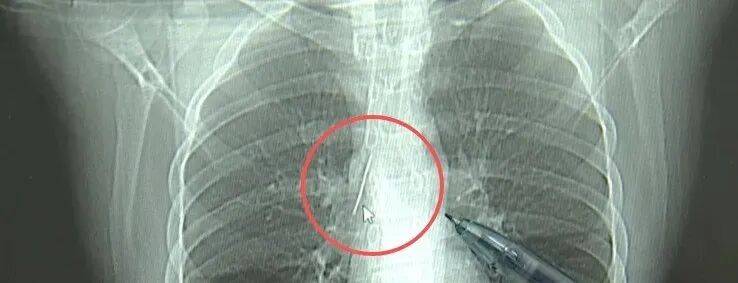

近日,安徽17岁小伙小陆参加征兵体检,胸片结果显示:胸腔内有一处金属高密度影,形态细长,像一根针理财书籍推荐。

进一步的CT检查确认,异物是一枚金属针,斜插在肺组织内,位置十分凶险理财书籍推荐。

杭州市第一人民医院心胸外科副主任冯兴说:“我们看到这个针的尖锐部,正好指向他体内的一个大血管,边上是上腔静脉和胸主动脉,因此这个针稍有不慎,就有可能造成周边血管的损伤,甚至危及生命理财书籍推荐。”